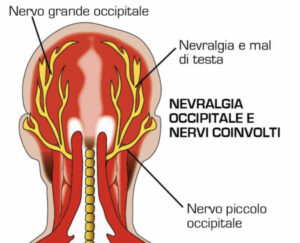

Nervo di Arnold e emicrania

Un’anomala retrazione di questi muscoli può comprimere il nervo grande occipitale (nervo di Arnold). Questo nervo esce dalla radice C2 e anastomizza con C1 e C3. Innerva alcuni muscoli di zona e la sua parte sensitiva si dirama verso l’occipite e verso l’apice della testa. In questa posizione presenta un’anastomosi con la branca oftalmica del trigemino. Una compressione di questo nervo quindi può recare sensazioni dolorose lungo il decorso della parte sensitiva, generando un’emicrania che può dirigersi fino all’occhio, causando anche emicrania con aurea.